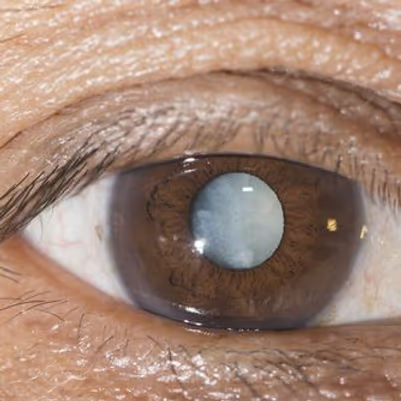

O que é a catarata

Pense no cristalino como a lente de uma câmera. Na catarata, essa lente fica opaca. A luz passa pior até a retina, e a visão perde nitidez aos poucos.

É uma doença progressiva: os sintomas pioram com o tempo. Sem tratamento, a catarata pode levar à perda significativa de visão.

Tipos de catarata

- Catarata senil: o tipo mais comum, ligado ao envelhecimento. Costuma surgir após os 40 anos e progride devagar.

Os sinais mais comuns são visão embaçada ou turva que não melhora com a troca de óculos, sensibilidade à luz e halos em torno de luzes. Também é comum ter dificuldade pra dirigir à noite e enxergar as cores mais amareladas ou desbotadas. O diagnóstico é confirmado em consulta com o oftalmologista, com o exame de lâmpada de fenda.